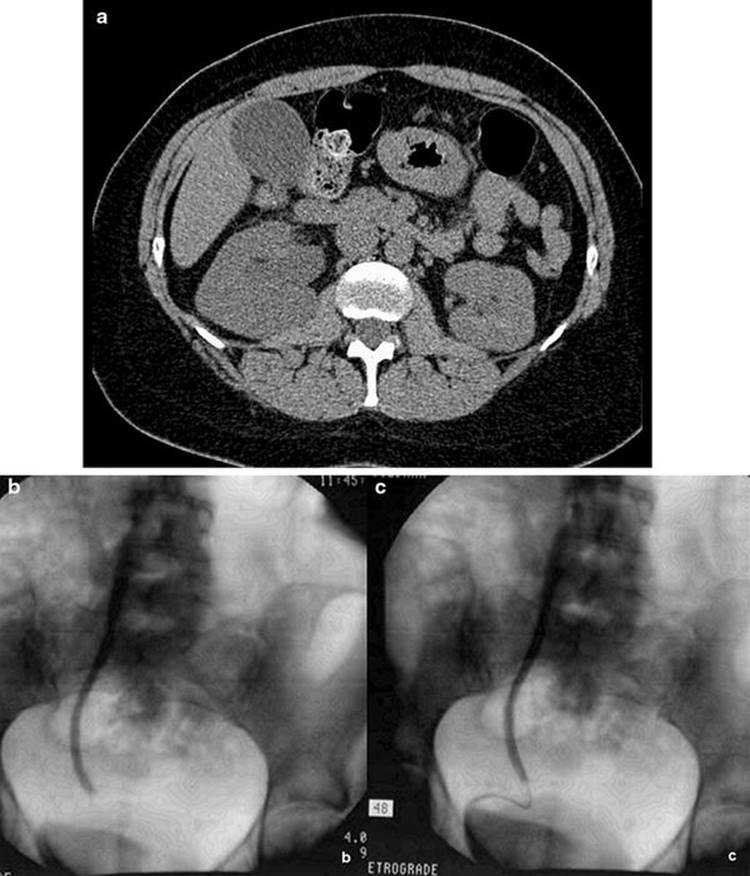

Ureteral injury is a potential complication of uterosacral colpopexy even when intraoperative cystoscopy reveals bilateral ureteral efflux. So-called “delayed obstruction” may occur due to excessive scarring between the uterosacral plication and the distal ureter, due to compromise of the ureteral blood supply or perhaps because of inadequate intraoperative examination for efflux. Ureteral obstruction presents in the acute postoperative period with flank pain, nausea and vomiting, and potentially fever. The diagnosis should be confirmed with imaging, and the study of choice in patients with normal renal function is CT Urography (CTU, see Fig. 5.2). The severity of hydronephrosis, site of ureteral obstruction, presence and location of any extravasation, presence or size of a potential urinoma, and the status of the contralateral kidney can all be assessed with a CTU. Once identified, in the acute postoperative period (up to 7 days), cutting the offending colpopexy sutures may be sufficient to relieve the obstruction. It is usually ideal to perform this in the operating room for several reasons. Aside from patient comfort, under anesthesia cystoscopy and retrograde ureteropyelography can be performed at the same time, to confirm patency of the ureter following removal of the suture(s). In addition, given the potential for ureteral edema and the severity of the obstruction, many urologists would choose to place an indwelling ureteral stent after relief of the obstruction. With further delay in presentation or failure to unobstruct in this manner, open abdominal or laparoscopic ureterolysis and reimplant is often necessary, although transvaginal ureterolysis and retrograde stenting has also been reported [5]. In a meta-analysis of USVVS, there was a 1.8% rate of ureteral obstruction, of which 2/3 resolved with suture removal, and the remainder required ureteral reimplantation [6].

Fig. 5.2

A woman with postoperative suspicion of ureteral injury is found to have right hydronephrosis on a CT (a). Right retrograde ureterography demonstrates medial deviation of the distal ureter, and the distal ureter is not opacified (b). A wire was successfully passed (c), over which a stent was then placed (photograph courtesy of Howard Goldman, MD, Cleveland Clinic, OH)